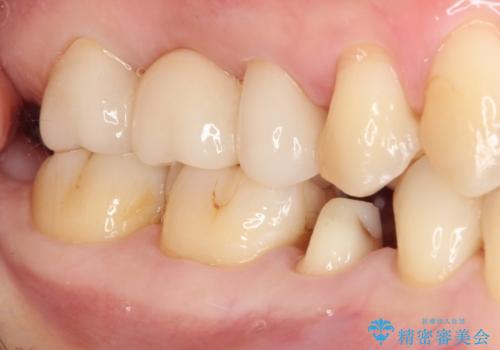

以前治療した詰め物が欠けた オールセラミッククラウンによる補綴

- 他院にて治療した詰め物が欠けてしまった事を主訴に来院された患者様です。

詰め物の範囲が大きく、部分的な詰め物では再び割れてしまうリスクが高いため、

オールセラミッククラウンにて補綴することとしました。

しみる症状はなくなり、見た目もきれいになり、とても満足されました。